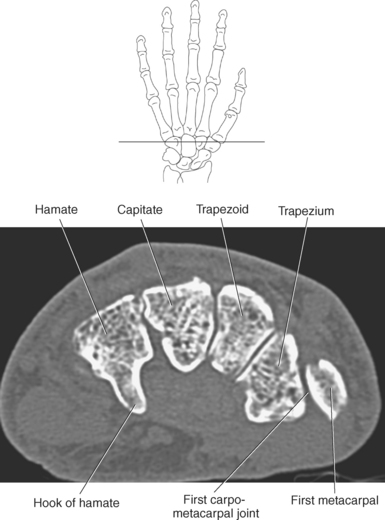

The bony anatomy of the wrist and hand consists of the distal radius and ulna, 8 carpal bones, 5 metacarpals, and 14 phalanges (Figure 9.101). Both the distal radius and ulna have a conical styloid process that acts as an attachment site for ligaments. The radial styloid process is located on the lateral surface of the radius, whereas the ulnar styloid process is located on the posteromedial side of the ulna. The carpal bones are arranged in proximal and distal rows. Located in the proximal row of carpal bones are the scaphoid (navicular), lunate (semilunar), triquetral (triquetrum), and pisiform bones. The pisiform is considered a sesamoid bone that is embedded in the tendon of the flexor carpi ulnaris. The distal row consists of the trapezium (greater multangular), trapezoid (lesser multangular), capitate (os magnum), and hamate (unciform) bones (Figures 9.102 through 9.114). The five metacarpals are small tubular bones with a proximal end (base), distal end (head), and shaft (body). The 14 phalanges that make up the fingers are short tubular bones. Like the metacarpals, each phalanx consists of a proximal (base), middle (body or diaphysis), and distal (head) portion. Each digit consists of 3 phalanges (proximal, middle, and distal), except for the thumb (first digit), which has only 2 phalanges (proximal and distal). The articulation of the phalanges of the second through fifth digits creates three interphalangeal joints: the metacarpophalangeal (MCP) joints classified as condyloid joints, proximal interphalangeal (PIP), and distal interphalangeal (DIP). The proximal and distal interphalangeal joints are classified as hinge joints (Figure 9.101). The first digit, which consists of 2 phalanges, has just two joints: the MCP joint, classified as a saddle joint, and an interphalangeal joint, classified as a hinge joint (Figure 9.101).

The joints of the wrist and hand are quite complex and consist of the following: distal radioulnar articulation, radiocarpal articulation (proximal joint of hand), midcarpal articulation (distal joint of hand), intercarpal articulations (articulations between proximal and distal carpals), carpometacarpal articulations (between carpals and metacarpals), the intermetacarpal articulations (between bases of metacarpals two through five) and the interphalangeal joints (between phalanges of each digit) (Figures 9.111 and 9.115). The distal radioulnar articulation, also called the distal radioulnar joint (DRUJ), is created when the ulnar notch of the radius moves around the articular circumference of the ulna, providing the movements of supination and pronation. The main stabilizing element of the DRUJ is an articular disk called the triangular fibrocartilage complex (TFCC). The TFCC is a fan-shaped band of fibrous tissue that originates on the medial surface of the distal radius and traverses horizontally to insert on the ulnar styloid process (Figures 9.115 and 9.116). It rotates against the distal surface of the ulnar head during pronation and supination and separates the ulna from the carpal bones. The proximal surface of the radiocarpal articulation is formed by the articular carpal surface of the radius and the TFCC, whereas the distal surface is formed by the articular surfaces of the scaphoid, lunate, and triquetrum and the interosseous ligaments connecting them (Figures 9.111 through 9.115). The midcarpal joint is formed by the articulations between the proximal and distal carpal rows (Figures 9.110 and 9.115). The articulation between the carpals within each row creates the intercarpal joints (Figures 9.111 and 9.115). The carpometacarpal joints are formed by the articulations between the carpus and the five metacarpals (Figure 9.111 and 9.115). The carpometacarpal joint of the thumb is an independent joint formed by the articular surfaces of the trapezium and first metacarpal, creating a pure saddle joint. The carpometacarpal articulations of the two to five digits are amphiarthrotic joints with little mobility (Figures 9.105 and 9.115). The intermetacarpal articulation exists between the base of the metacarpals and is joined by the palmar and dorsal metacarpal ligaments (Figure 9.115).